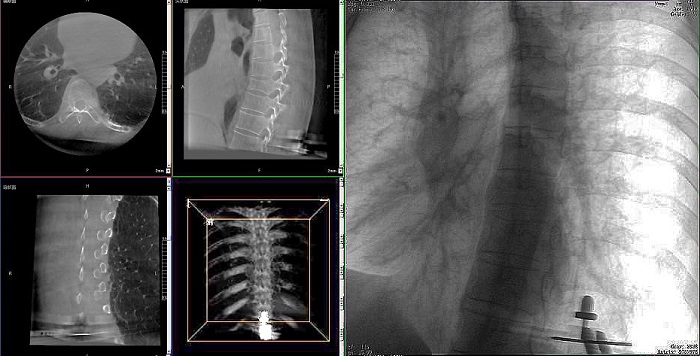

①機器人輔助胸椎手術操作難點之圖像采集

胸椎緊鄰肺部,患者的呼吸運動會造成椎節的相對移動,獲取清晰、穩定的影像較為困難。高質量的影像是精準導航的重要前提,胸椎手術中,如果呼吸造成的移動無法得到有效控制,則會降低導航的精度,增加手術風險。人體深吸氣胸圍與深呼氣胸圍的差值約為6~8厘米。

高清三維成像:普愛醫療精研三維成像技術13年,自研的三維C形臂可為手術提供清晰、穩定的三維圖像,為醫生精準開展胸椎手術提供影像保障。

快速掃描:麻醉師通過適當的呼吸控制,配合三維C形臂的快速掃描模式,可以在短時間內完成圖像采集,減少因呼吸運動造成的圖像干擾。